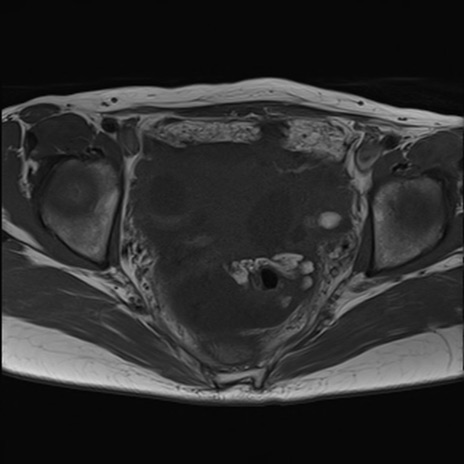

MRI(4日後)

【症例】40歳代女性

【主訴】上下腹部痛

【現病歴】2日目から下腹部痛あり。夜間は痛みで眠れなかった。昨日より上腹部痛と下痢が出現。臥位で痛みは軽快したため、休んでいた。本日になって臥位でも立位でも痛みが強くなってきたため救急要請。

【既往歴】子宮内膜症

【身体所見】部:平坦・軟、左上下腹部に圧痛あり、反跳痛あり。

【データ】WBC 21800、CRP 26.78